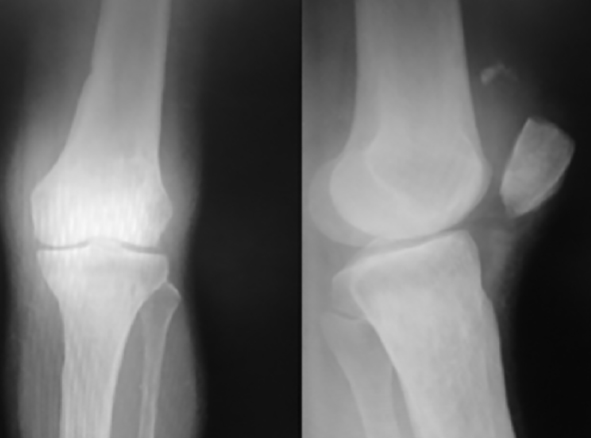

El segundo caso corresponde a un paciente varón de 33 años, con secuelas de polio en miembro inferior izquierdo que, previamente, deambulaba sin soportes y presentó una ruptura del tendón patelar abierta con avulsión, pérdida tendinosa y déficit de recubrimiento en la tuberosidad tibial anterior. Como trauma asociado presentó una luxación cerrada de la cadera ipsilateral secundaria a un accidente de tránsito como motociclista (Figura 2). A este paciente se le realizó una reducción cerrada de la cadera en el servicio de urgencias y, posteriormente, se reconstruyó el tendón patelar con injerto TC. En este caso, adicionalmente al cerclaje de alambre, se realizó aumentación con tendón del músculo semitendinoso preservando su inserción distal. Dado el déficit de recubrimiento se decidió rotar un colgajo del músculo gastrocnemio medial que se injertó con piel del mismo paciente.

Por medio de un abordaje anterior de rodilla, se expuso de forma completa el mecanismo extensor, con los hallazgos descritos. Dada la pérdida importante de tejido tendinoso, se decidió emplear el tendón del músculo cuadricipital aprovechando la osteointegración directa y la fijación estable que proporciona el taco óseo de este injerto. Se resecaron 5 cm del m. recto anterior dejando indemne el recto intermedio con un taco óseo del polo superior de la patela, 2x1 cm, con sierra oscilante. La parte tendinosa se solidarizó al tendón remanente con sutura 1/0 (Ethibond®), efectuando puntos de Krakow. Aprovechando la longitud del injerto se pasaron hilos de sutura a través de la patela, utilizando la guía con ojal empleada en cirugía de cruzado anterior, efectuando tres túneles y dejando 6 cabos de sutura para afrontarlas posteriormente en el polo superior de la patela (Figura 2). La porción ósea del injerto se fijó en un lecho de las mismas dimensiones en la tuberosidad anterior de la tibia (labrada previamente con uso de sierra oscilante) y un tornillo cortical con arandela con técnica de compresión interfragmentaria (Figura 2), logrando llenar adecuadamente el defecto tendinoso. En ambos casos se efectuó un cerclaje circular con alambre y en el segundo caso, dada la pérdida masiva, se reforzó adicionalmente con cerclaje circular de tendón del m. semitendinoso (Figura 2). En ambos casos se permitió la movilidad y el apoyo temprano con protocolo profiláctico de anticoagulación.